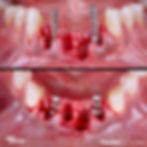

Minimally post extractive technique/periodontal condition/ GBR soft tissue management.

INITIAL CONDITION

SURGICAL APPROACH

IMMEDIATE IMPLANT PLACEMENT [PRIMARY STABILITY]

SOFT TISSUE MANAGEMENT - Healing screw during preparation of temporary prosthesis